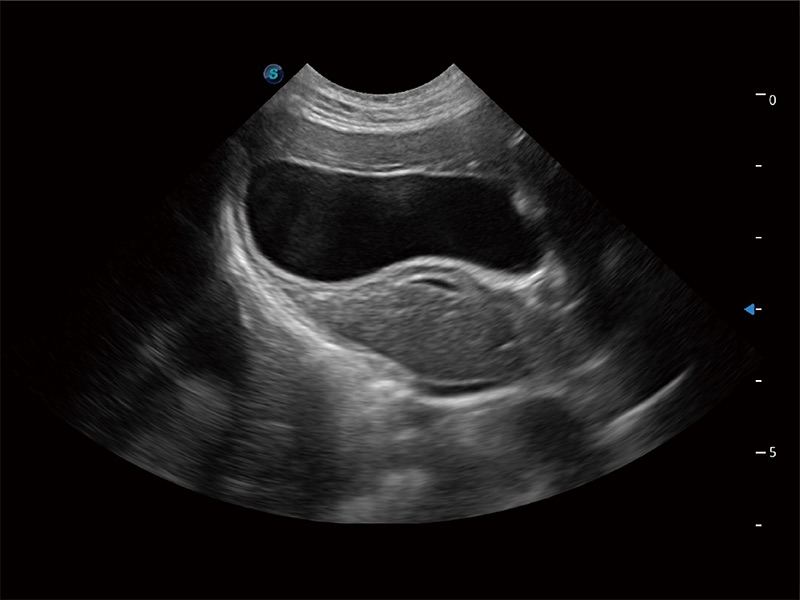

动物是人类最亲密的朋友和最值得信赖的伙伴。milan米兰也一直致力于探索动物专用的超声影像解决方案。全新推出的ProPet系列,是milan米兰在动物超声影像智能化、专业化、精准化的一次跨越式革新。动物不能用言语来表述自己的不适,通过超声影像,ProPet系列搭建了动物医生与不同物种沟通的“桥梁”,为动物医生注入了“治愈之力”。 ProPet 80 是milan米兰匠心打造的一款高端动物专用彩超,采用性能卓越的全新硬件架构,极大提升超声系统的运行效率和数据处理能力,帮助动物医生从容应对日益增多的挑战性病例和日益多样化的临床需求。

高性能和先进的临床应用工具可以为动物医生提供临床信心。ProPet 80 搭载了先进的腹部和浅表应用工具,帮助医生在日常临床实践中发挥前所未有的作用。

一键自动识别膀胱壁及自动测量膀胱容积,不受膀胱形状和大小的限制,帮助医生快速精准获得测量的数据。